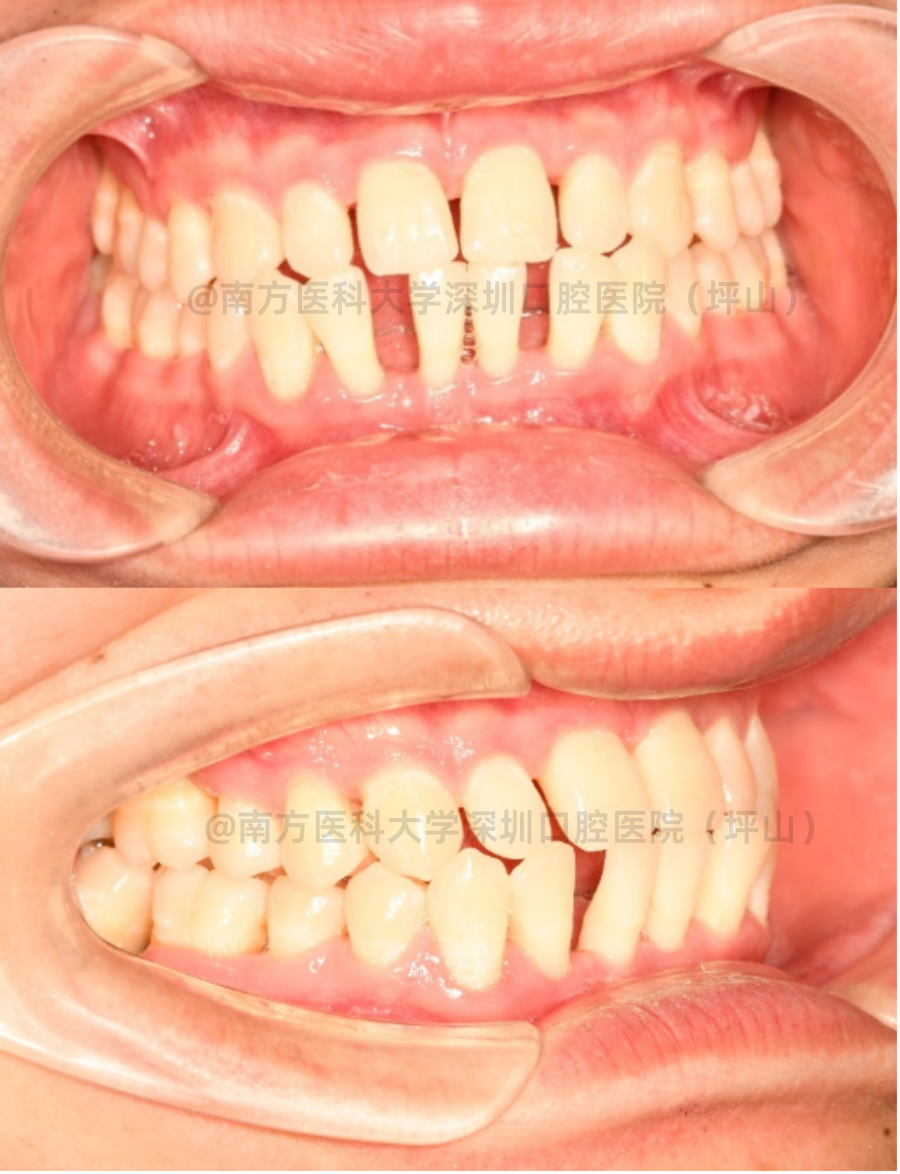

待牙周状态稳定后,谢先生在正畸科刘慧君医生处接受了全口固定矫治。

刘医生为他做的第一步是𬌗垫治疗,目的是去除前牙的异常咬合力(咬合干扰),避免牙缝继续变大、牙齿松动。

随后在全口牙齿上粘金属自锁托槽,逐步排齐牙齿,关闭牙齿间隙,建立正常的咬合。在每个月的复诊中,给予恰当的咬合力,精细调整全口咬合,形成广泛均匀的咬合基础。

虽然经过规范治疗以后,可以控制牙周炎的进展,但是已被破坏的软硬组织难以恢复到正常状态。

由于患者的牙周状态仍然很脆弱,重度牙周病患者的正畸治疗过程犹如“走钢丝”,要求正畸医生胆大心细,仔细检查每颗牙齿的状态及牙齿咬合情况,然后在每颗牙齿上施加适当的矫治力。同时,仍需定期复查牙周情况。

整个矫正时间历时1年4个月,通过医生及患者的积极配合,最终达到了患者满意的效果。